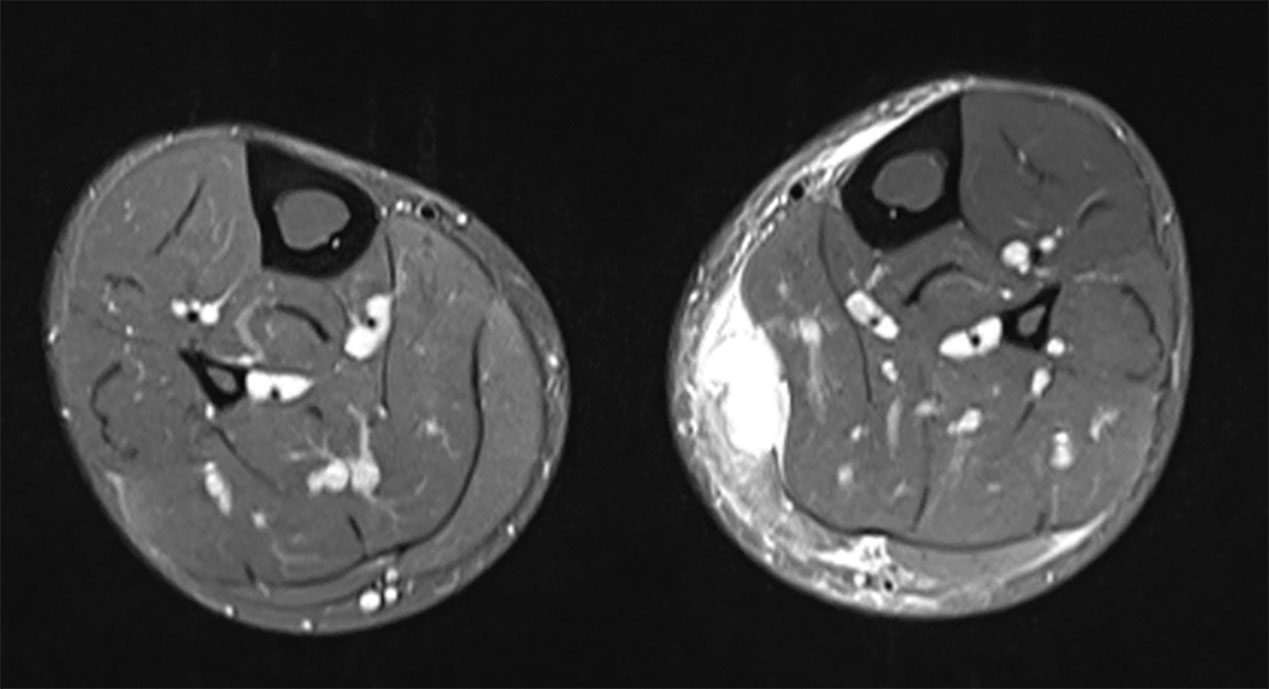

The MRI scans of the left lower leg obtained after the injury demonstrated a substantial, semi-circumferential medial fluid collection along the superficial soleus fascia. There was oedema within the medial head of the gastrocnemius which showed a circumscribed haematoma measuring 12 x 29 mm. In addition, there was an extensive lamella of fluid extending to the anterior margin of the tibia. The retracted tendon core of the medial head of the gastrocnemius was evident at the inferior margin of the haematoma, at the level of the middle third of the tibial shaft (Figs. 1 + 2).